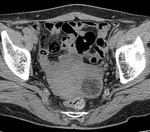

[画像診断]PTP誤嚥について